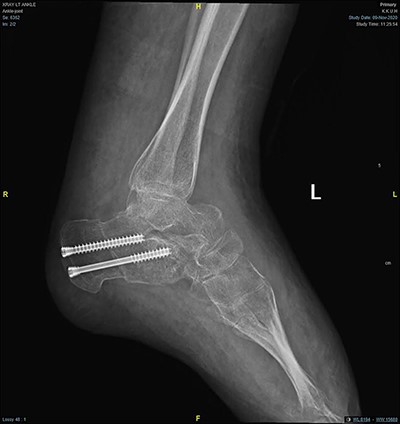

Lateral foot radiograph showing correction of the deformity after calcenus osteotomy.

In the operation room, the patient was placed prone, then supine on a radiolucent table under general anesthesia. A tourniquet was placed below the fibular head without Esmark. Tourniquet compression was suggested by the vascular surgeon due to her deep vein malformations. We started our procedure with a standard posteromedial approach. Percutaneous Achilles tendon lengthening by triple hemisectiontendon and isolation of the posterior tibial tendon were done. Another medial ankle approach was done to incise the posterior tibial tendon from its insertion at the navicular. Extensive venous plexus was noticed in the midfoot, which was isolated and protected. Posterior tibial tendon transfer anteriorly through the interosseous membrane. Lateral sliding calcaneal osteotomy was done through lateral calcaneal approach and fixed with two 5.0 mm cannulated headless screws under image guide (Figs 4 and 5). In addition, two incisions were done at the dorsum of the midfoot and the anterior distal one-third of the left leg corresponding to the reflected posterior tibial tendon from posterior to anterior. The tendon was then passed under the extensor retinaculum and delivered in the dorsum of the midfoot. Sutures anchors were used to fix the tendon in the lateral cuneiform. Finally, planter release was done for all five toes through snip penetration with 11 blades. The overall correction was found acceptable intraoperatively. All incisions were then closed in layers. Then, she was placed on a controlled ankle motion boot (CAM boot) for 3 days to allow for swelling, followed by a U-shape and backslap splint. She was kept non-weight bearing for 6 weeks to allow for bone healing. After 6 weeks, the protocol was advancing the weight-bearing status from non-weight bearing to partial to full weight-bearing as tolerated with the CAM boot. Moreover, gait and range of motion exercises were started around the tenth week. The patient reported significant improvement in her ability to walk and overall satisfaction with the surgery at the fourth month postoperative (Fig. 6).